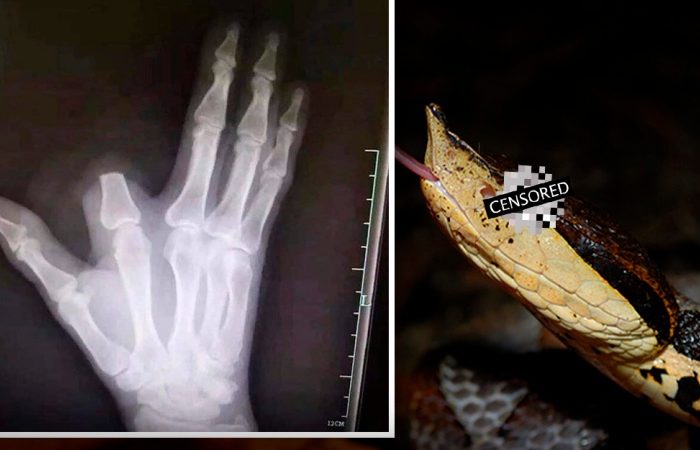

ชายโดนงูพิษร้ายแรงกัดนิ้ว ตามตำนานเค้าบอกให้ตัดนิ้ว เพื่อรักษาชีวิต เลยทำตาม ก่อนหมอจะบอก ไม่จำเป็นต้องตัดก็ได้

เหตุการณ์นี้เกิดขึ้นที่จีนครับ วันหนึ่งนาย...